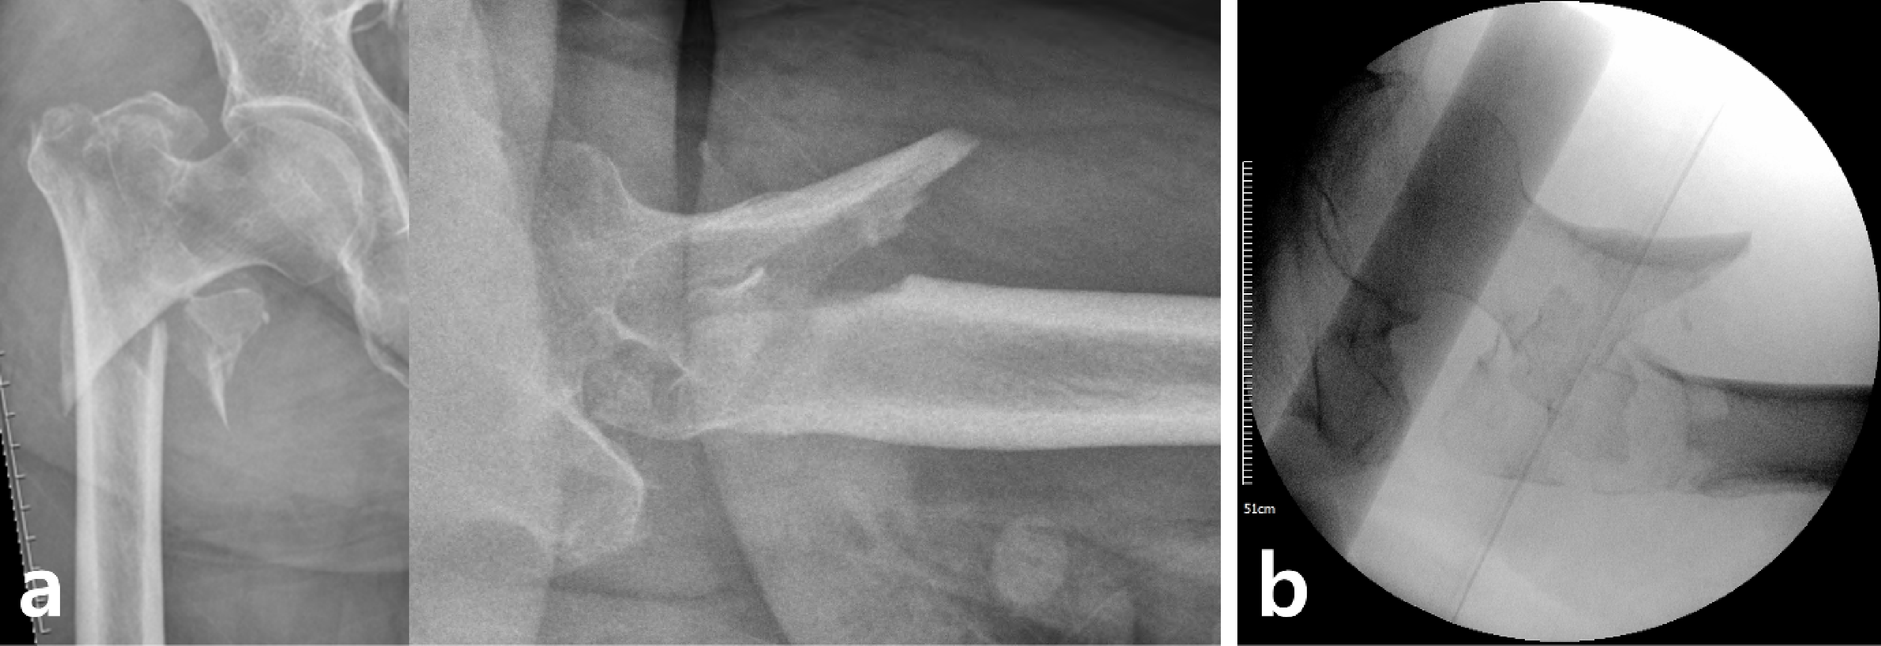

Fig. 1

Sagittally unstable intertrochanteric fracture (SUITF). (a) Preoperative anteroposterior and translateral radiograph of hip presenting morphological characteristics of SUITF. (b) Intraoperative radiograph demonstrates posterior sagging of the SUITF despite traction.